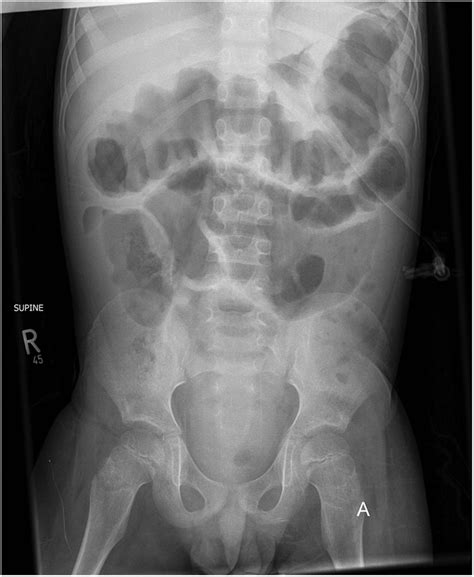

Ulcerative Colitis Xray . Web radiographical modalities have become important diagnostic tools in cases of ulcerative colitis (uc). Web learn how doctors use colonoscopies, ct scans, mri scans, and other methods to diagnose uc, a form of inflammatory bowel disease.

Web radiographical modalities have become important diagnostic tools in cases of ulcerative colitis (uc). Web learn how doctors use colonoscopies, ct scans, mri scans, and other methods to diagnose uc, a form of inflammatory bowel disease. Web ulcerative colitis is one of the two main subtypes of inflammatory bowel disease, along with crohn's disease.

Traditionally, barium enema examination has been the mainstay of radiologic investigation. Traditionally, barium enema examination has been the mainstay of radiologic investigation. Web ulcerative colitis is one of the two main subtypes of inflammatory bowel disease, along with crohn's disease. Web learn how doctors use colonoscopies, ct scans, mri scans, and other methods to diagnose uc, a form of inflammatory bowel disease.